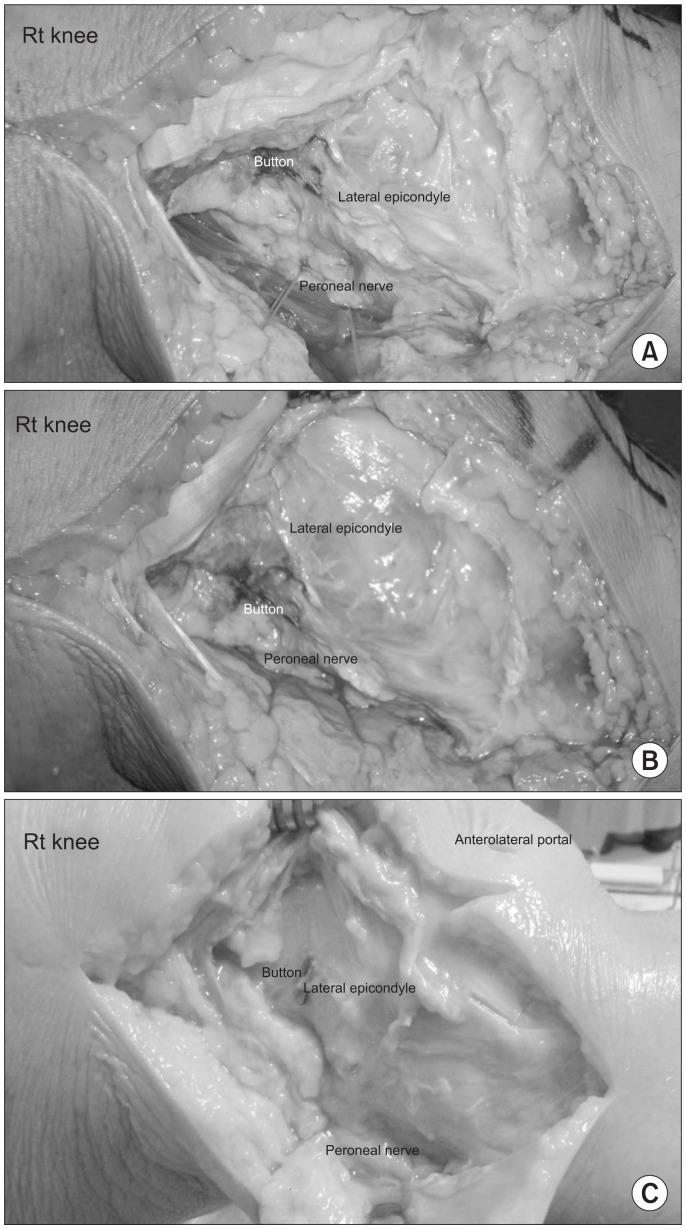

Three different suspensory devices (TightRope RT, RetroButton, and EndoButton) were used in ACL reconstruction using 3 different techniques (outside-in, anteromedial [AM] portal, and transtibial techniques). Positioning of a guiding material and seating pattern of the suspensory devices were evaluated according to the surgical technique and suspensory device used.

On the transtibial technique, 21 of total 26 cases (81%) of single bundle reconstructions and 22 of total 22 cases (100%) of double bundle reconstructions required superolateral capsulotomy where buttons were found in 21 of total 21 cases (100%) and 17 of 22 cases (77%), respectively. On the AM portal technique, all patients required capsulotomy and the button was found in only 18 of total 32 cases (56%) even after capsulotomy. On the outside-in technique, all patients required capsulotomy and the button was found in 86 of total 86 cases (100%).

Our technique for direct visualization of seating of the suspensory devices was more effective in outside-in and single bundle transtibial ACL reconstruction. However, it was less effective in double bundle transtibial and AM portal ACL reconstructions.